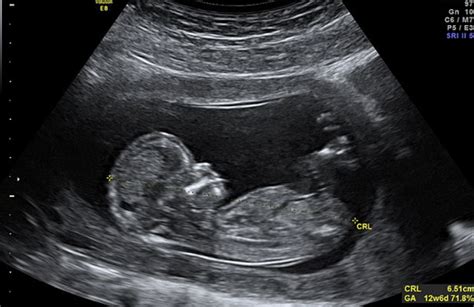

Lunghezza Vertice-Sacro (Crown-Rump Length, CRL): Durante il primo trimestre e all’inizio del secondo, la dimensione principale da tenere sotto controllo è il valore che si ottiene misurando dalla testa fino all’osso sacro. Il valore del CRL è particolarmente importante nel primo trimestre per datare la gravidanza in modo preciso. Per monitorare l'andamento del diametro biparietale (BPD) nel primo trimestre, si fa riferimento a studi come quello del gruppo di Yves Ville, pubblicato nel 2003. Nella gravidanza iniziale, una tabella che riporta le misure medie di frequenza cardiaca (Embryonic Heart Rate), diametro del sacco gestazionale (GSD gestational sac diameter), e diametro del sacco vitellino (YSD yolk sac diameter) è correlata alle dimensioni dell’embrione (CRL).